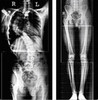

У меня проблема в том, что с правой стороны пениса появилось внутреннее утолщение. Плотность. При эрекции половой член немного изгибается в сторону. Последнее время чуствую небольшой дискомфорт, чуть болезненные ощущения. Что это? И к какому врачу обратиться?

Здравствуйте! Возможно у Вас болезнь Пейрони. Вы можете обратиться ко мне на консультацию, при осмотре можно будет выполнить все необходимые анализы и в том числе УЗИ допплер полового члена, после определимся с лечением.